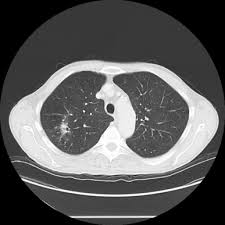

Emphysema is defined as abnormal, permanent enlargement of airspaces distal to the terminal bronchioles and accompanied by the destruction of airspace walls without obvious fibrosis.the main purpose of radiographs in emphysema patients is to exclude comorbidities such as pneumonia, pulmonary oedema, lung cancer, and so on.we are already well informed of the image findings of emphysema and. Can lung cancer be mistaken for copd? That's because the symptoms of emphysema can easily conceal copd, and copd can conceal the presence of lung cancer. Pancreatic cancer may be diagnosed as diabetes, due to the fact that diabetes is often a symptom or risk factor of pancreatic cancer. Malignant tumors trigger inflammation in surrounding normal lung tissue, and they may obstruct your airways and interfere with normal airflow.